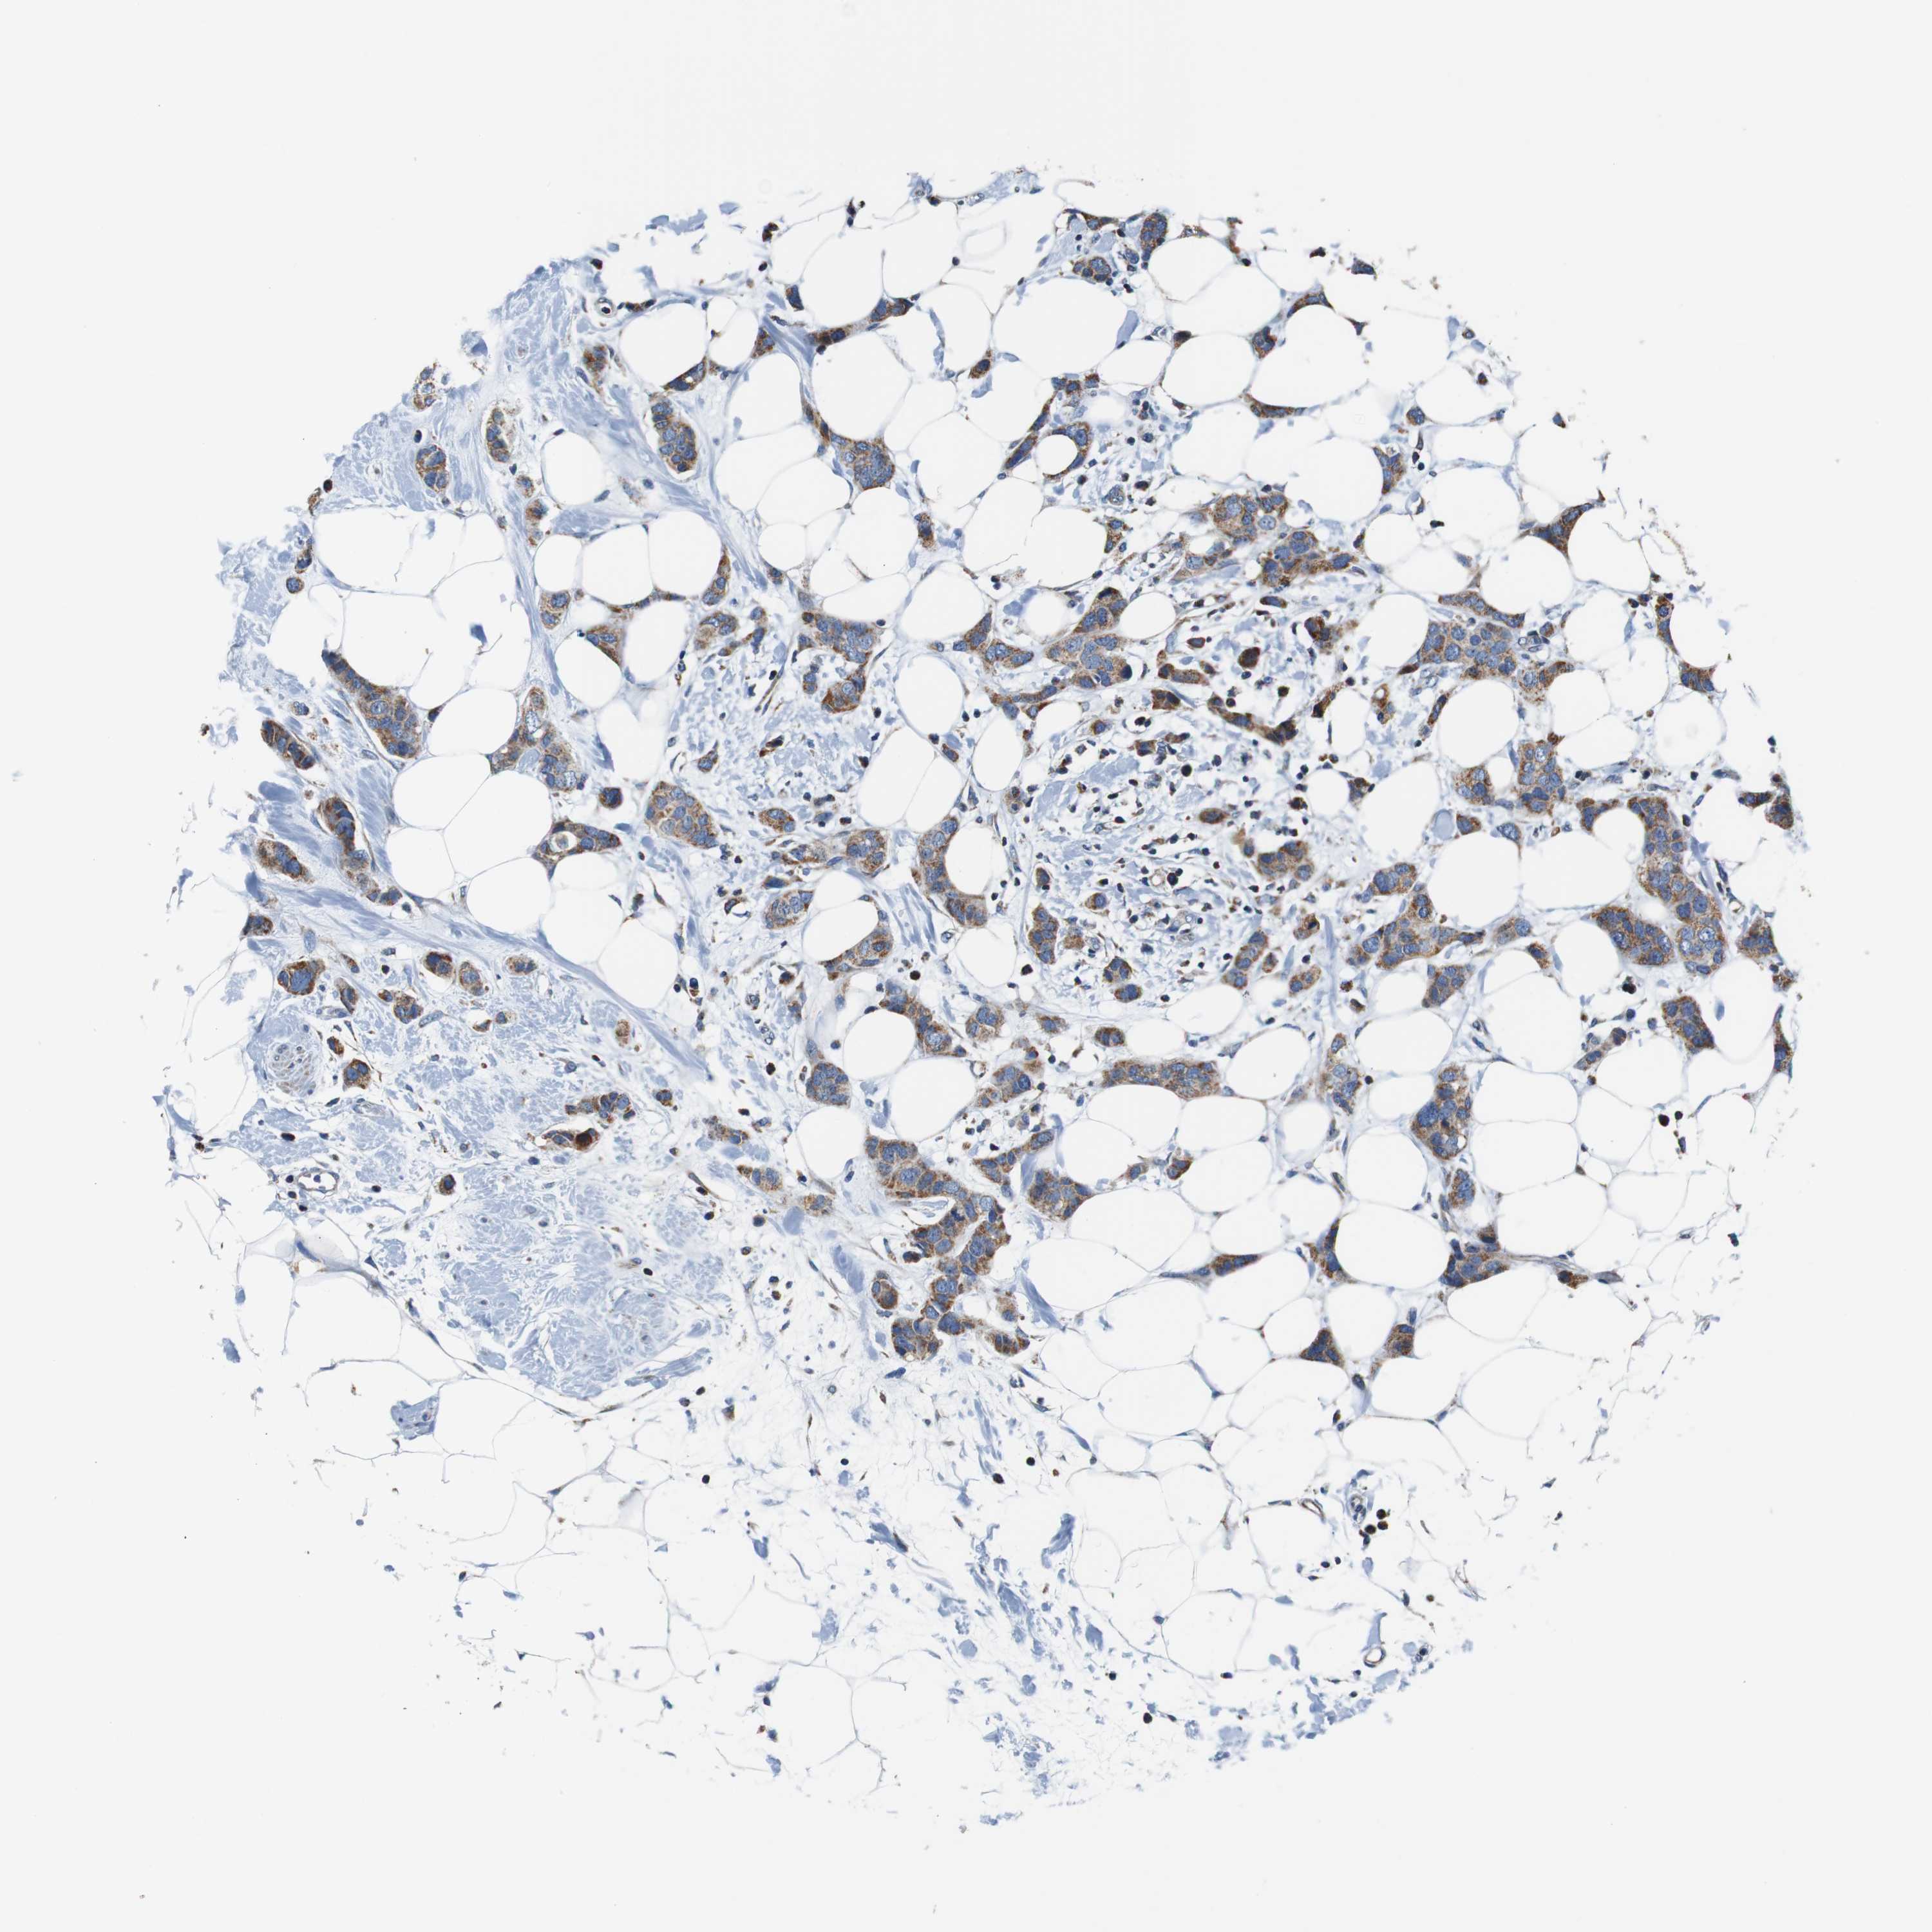

CANCER BREAST CANCER Show tissue menu

BRCA TCGA BRCA VALIDATION PROTEIN EXPRESSION